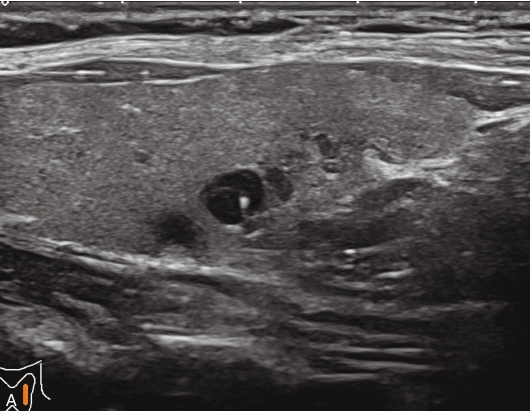

甲状腺左叶下极可见一低回声结节,大小约1.2cm×1.0cm×1.0cm,边界清楚,内未见强回声。CDFI显示甲状腺左叶下极结节内部及周边均未见血流信号,见图1-3-5。

图1-3-5 常规超声声像图

A.甲状腺左叶横切面超声图像;B.甲状腺左叶纵切面超声图像

甲状腺左叶下极结节超声造影全程呈整体无增强,病灶边界清楚,无增强面积等于灰阶超声所示,见图1-3-6、ER1-3-3。